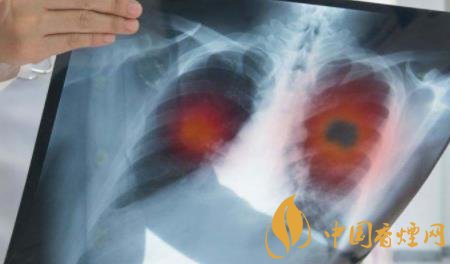

2、長(zhǎng)期吸煙危害肺部健康

吸煙會(huì)產(chǎn)生大量的煙霧,而這些煙霧中含有大量的有害物質(zhì),如焦油、尼古丁、一氧化碳等成分,每當(dāng)你抽煙的時(shí)候,這些毒素就會(huì)隨著煙霧進(jìn)入到肺部,如果長(zhǎng)時(shí)間抽煙的話,這些毒素就會(huì)在肺部里積便越來(lái)越多,會(huì)打破肺部功能的自身紊亂,使肺部無(wú)法正常的活動(dòng),會(huì)引發(fā)很多肺部疾病。